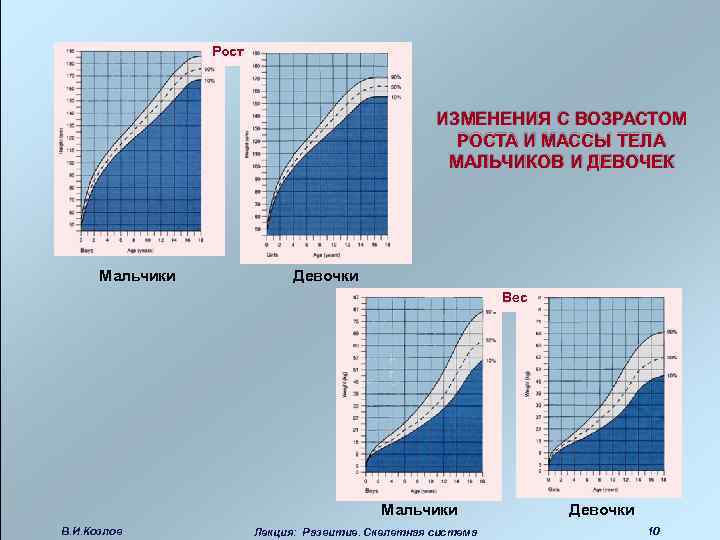

Рост ИЗМЕНЕНИЯ С ВОЗРАСТОМ РОСТА И МАССЫ ТЕЛА МАЛЬЧИКОВ И ДЕВОЧЕК Мальчики Девочки Вес Мальчики В. И. Козлов Лекция: Развитие. Скелетная система Девочки 10